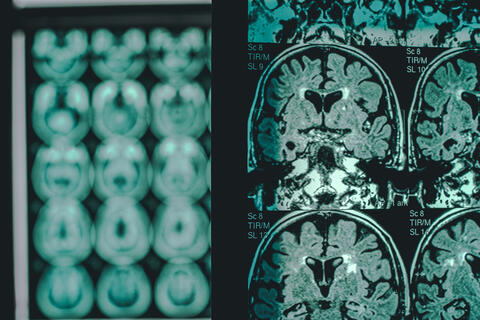

MRI scan of a brain with Alzheimer's disease.

Research |

Study, published this month in Communications Biology, reveals that chronic hyperglycemia impairs memory.